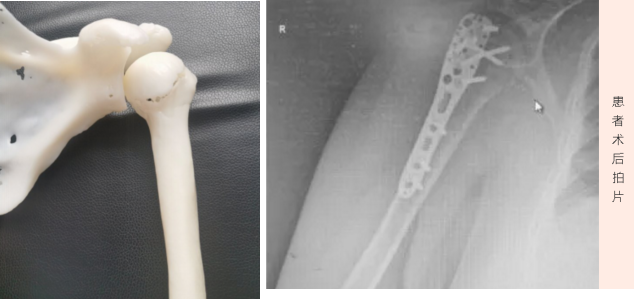

3D打印骨科手术

近期,莱州市中医医院骨伤一科团队成功完成一例3D打印骨科手术,3D打印精准医学首次实践应用,标志着正式进入3D打印精准医学时代,这在骨科发展道路上具有里程碑意义,也必将在发展史上写下浓墨重彩的一笔。